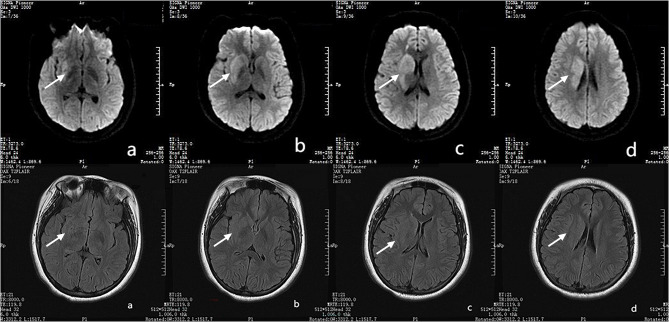

Case description: A pediatric patient presented with AIS involving the left limb, lasting 2.5 h. The stroke occurred during physical activity without loss of consciousness or seizures. Head magnetic resonance imaging (MRI) combined with clinical manifestations confirmed the diagnosis of acute cerebral infarction. Intravenous thrombolytic therapy using tenecteplase was initiated in the ultra-early phase of infarction. Subsequent cerebral angiography revealed occlusion of the superior trunk of the right middle cerebral artery. Three-dimensional rotational imaging identified multiple aneurysms at its bifurcation. A targeted intra-arterial injection of tirofiban (6 mL) was administered to stabilize plaque and enhance blood flow. The patient underwent 11 days of antiplatelet therapy and supportive care. At the 90-day postoperative follow-up, notable recovery of limb function was observed.